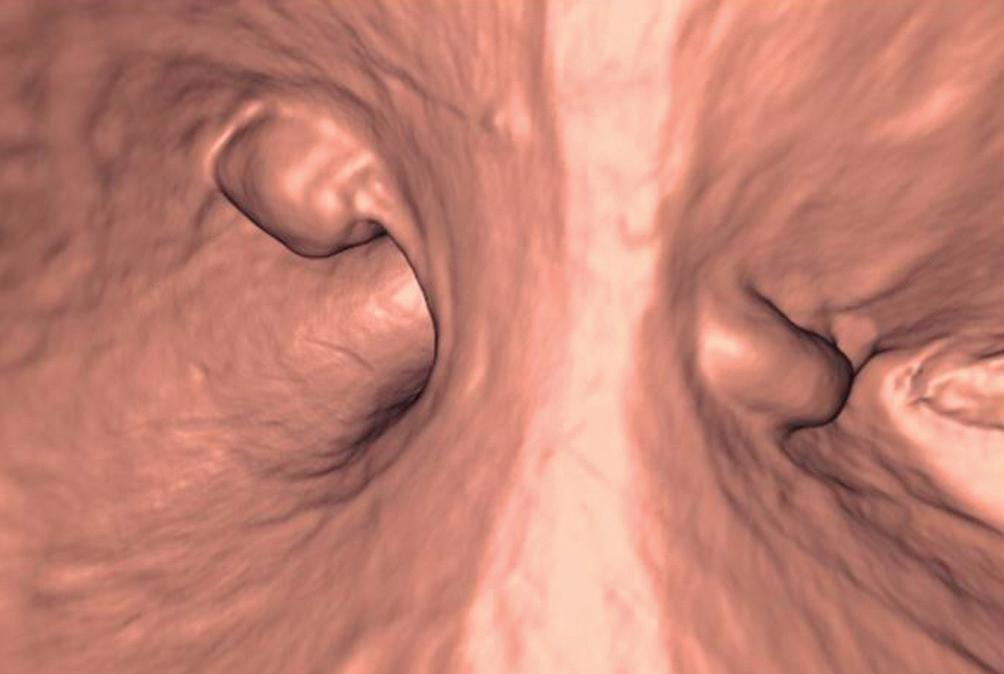

Evaluación de un paciente con dolor epigástrico y hallazgos sincrónicos infrecuentes

Roy López Grove, Daniela Soloaga, Juan Carlos Spina

Roy López Grove, Daniela Soloaga, Juan Carlos Spina 398